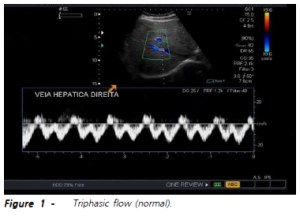

Στον έλεγχο της ροής της ηπατικής φλέβας ελέγχθηκε διαφορετική κυματομορφή ( to and fro)

από την φυσιολογική (triphasic).